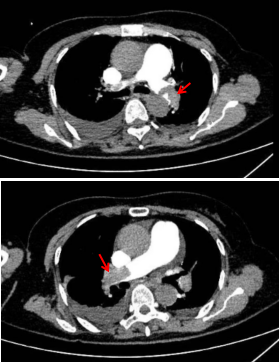

老年女性脑梗死恢复期患者,入院当日因出现呼吸困难、血氧饱和度下降,被紧急转入重症医学科。在给予经鼻加温湿化高流量氧疗、抗心力衰竭及抗凝等综合治疗后,患者症状仍未完全缓解。后续经床旁超声深入评估,高度提示急性肺动脉栓塞可能,随即进行的肺动脉CTA检查证实:患者左、右肺动脉主干及分支内可见多发条片状栓塞灶,病情危重,存在猝死风险。高志凌主任团队全面评估患者情况,判定其危险分层属于“中高危”,在与家属充分沟通并取得同意后,决定实施静脉溶栓治疗。12月17日21时起,团队开始为患者进行历时2小时的溶栓治疗,全程严密监测生命体征,并借助床旁超声等设备实时评估溶栓效果及可能出现的并发症。经过重症医学科全体医护人员精心治疗与护理,患者溶栓后氧合水平逐步提升,胸闷症状明显缓解。一周后复查肺动脉CTA显示,肺动脉内栓塞灶显著减少,肺叶血流供应基本恢复,患者终于转危为安。